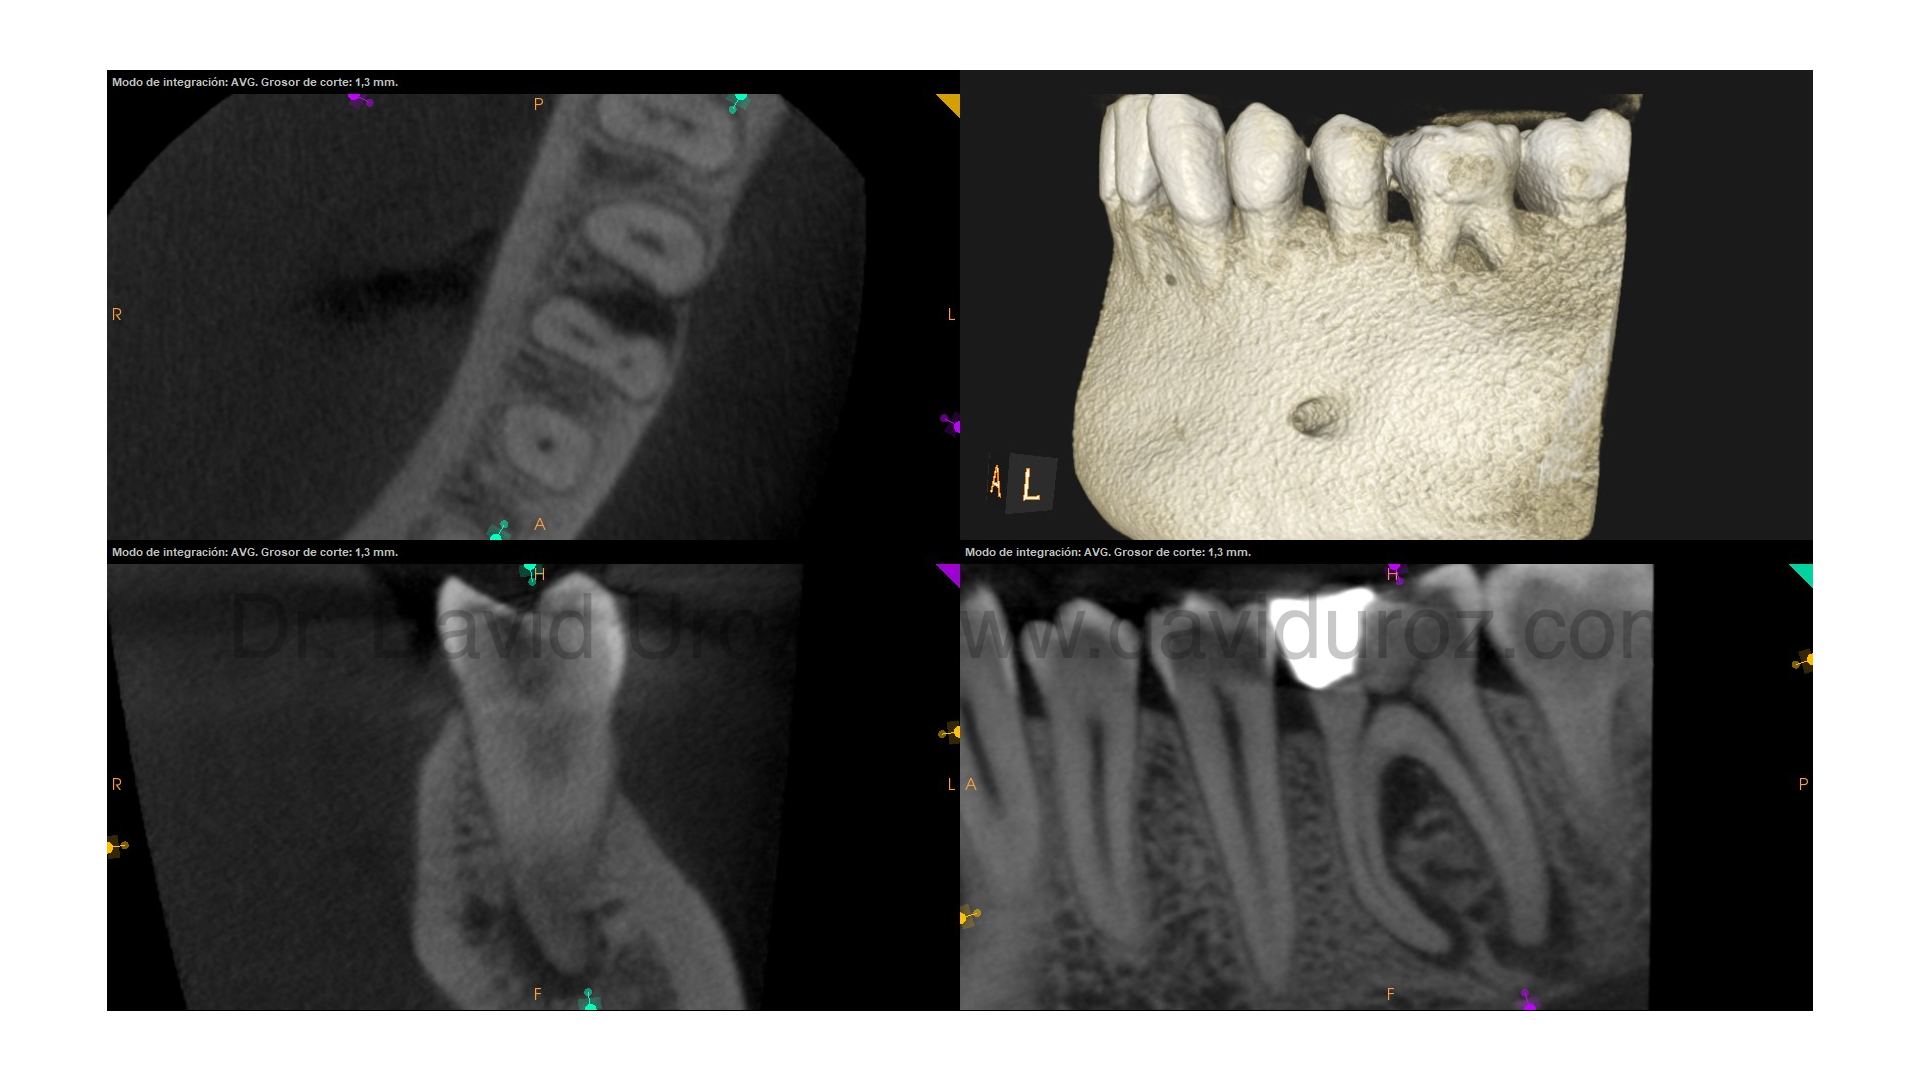

Comienzan a llegar los primeros casos a revisión de molares tratados con el nuevo sistema rotatorio de VDW, ROTATE. Uno de los grandes aciertos de este sistema es la introducción de una lima 25/04 que nos permite ser más conservadores en la zona de peligro. Se presenta un caso con signos claros de necrosis y periodontitis apical, con una lesión de furca. Descartada la fisura realizamos tratamiento de conductos con apertura proyectada, insistiendo en una buena desinfección, mediante activación del irrigante con sistema EDDY. La aparición del conducto lateral a nivel de tercio medio nos deja tranquilos de cara a esa lesión de furca. La revisión a 6 meses nos muestra un paciente asintomático, con curación de las lesiones apicales. Sin embargo el proceso restaurador está fracasando, la obturación mesial se encuentra fracturada (por suerte el sellado cameral con SDR evitó filtración bacteriana anivel de los conductos) y hubo un intento fallido de colocar un perno distal (en mi opinión innecesario), dejando burbujas en el posterior sellado. Se vuelve a remitir a su restaurador indicando la necesidad de nueva restauración y valoración de protección cuspídea.